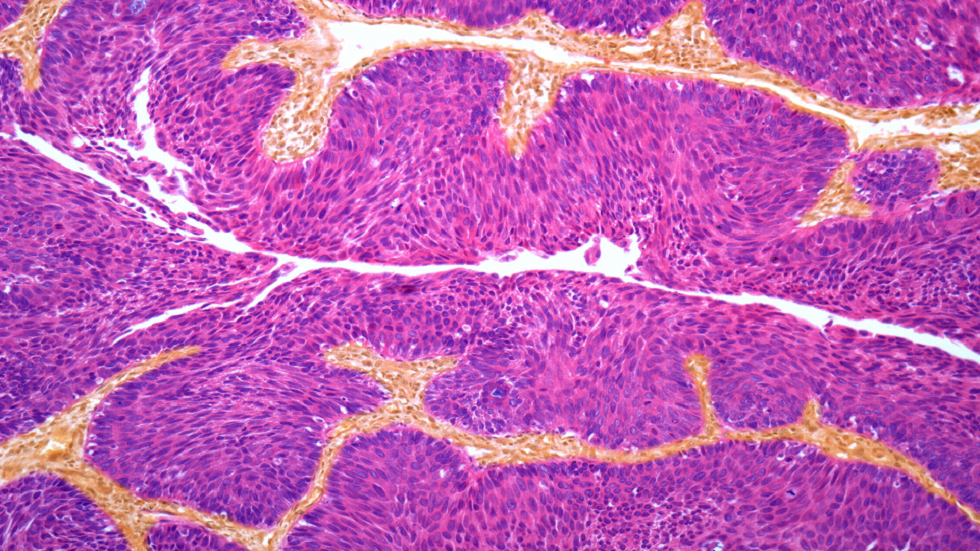

الموافقة على دواء جديد يمكنه تغيير حياة مرضى سرطان المثانة!

تلقى مرضى سرطان المثانة مؤخرا بعض الأخبار الإيجابية حيث تمت الموافقة على عقار جديد للاستخدام من قبل NHS.

وصمم العقار المعني، nivolumab، للمرضى الذين يعانون من الضعف الشديد للخضوع للعلاج الكيميائي أو الذين تكون الآثار الجانبية شديدة عليهم.

وأظهرت التجارب أن الدواء يمكن أن يمنع السرطان من العودة بعد إزالة الورم مع عدم ظهور علامات السرطان على بعض المرضى لمدة ثلاث سنوات على الأقل.

ويعمل الدواء عن طريق مساعدة جهاز المناعة في الجسم على البحث عن الخلايا السرطانية وتدميرها.

ورحّب بأخبار الموافقة على الدواء، بما في ذلك من قبل أخصائي الأورام البروفيسور توبياس أركيناو: "العديد من مرضى سرطان المثانة لدي لا يمكنهم تحمل العلاج الكيميائي. وهذا الدواء يعمل بشكل جيد للغاية وآثاره الجانبية أقل بشاعة".

ويتم علاج سرطان المثانة، تماما مثل أشكال السرطان الأخرى، بشكل أكثر فعالية عند تشخيصه مبكرا.